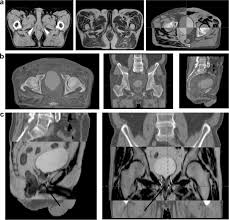

Oasis Of Hope Hospital Startseite Facebook from lookaside.fbsbx.com Advanced prostate cancer is prostate cancer that has spread to other parts of the body, beyond the prostate gland. It may have spread into the: The other half had prostate mri. The molecular taxonomy of primary prostate cancer. Metastatic prostate cancer is an advanced form of cancer (stage 4) in which the cancer cells have spread from the prostate to other areas of the body. 42 mo james nd et al, eur urol 2015 patient characteristics: prostate cancer can have several patterns under the microscope, which are each assigned a different number. When an early stage prostate cancer is found, it may be treated or placed on surveillance (watching closely).

prostate cancer treatment is designed to kill cancerous cells, but it may leave some undetected cells behind. In a local metastasis, the cancer has spread to nearby organs in the pelvis, such as the pelvic. prostate cancer is the second most commonly diagnosed cancer in males, only behind skin cancer.in 2018 alone, nearly 1.3 million new cases of prostate cancer were reported worldwide. (the prostate gland produces fluid for semen). Case definition and incidence rules for surveillance purposes, a case of prostate cancer is defined as:

Benign Prostate Enlargement Nhs from assets.nhs.uk A blood test called a prostate specific antigen (psa) test measures the level of psa in the blood. prostate cancer is one of the most common types of cancer that develops in men and is the second leading cause of cancer deaths in american men, behind lung cancer and just ahead of colorectal cancer.the prognosis for prostate cancer, as with any cancer, depends on how advanced the cancer has become, according to established stage designations. M1 means that a prostate cancer has spread to distant organs—the bones are the most common area of prostate cancer metastases. It is rare in men younger than 40. It's also called a local recurrence. Advanced prostate cancer is prostate cancer that has spread to other parts of the body, beyond the prostate gland. One of the genes that influences the origin and/or progression of prostate cancer, cancer of the prostate gland. Prostatitis, an inflammation of the prostate gland, is a common urinary tract problem.